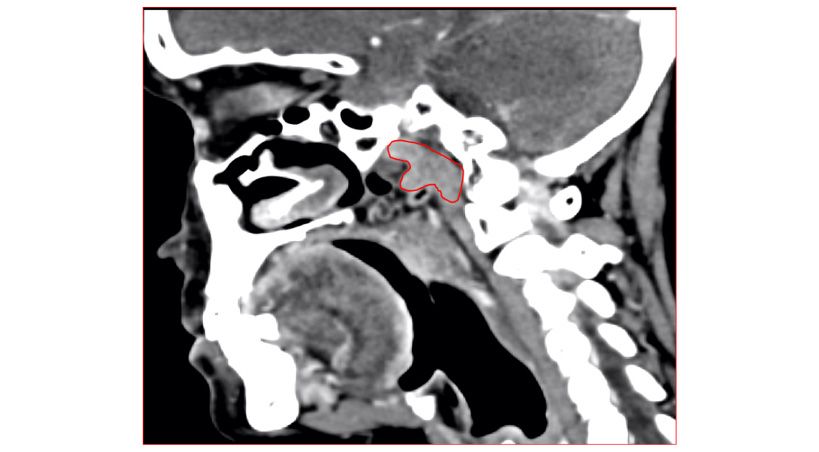

Reducción espontánea de fractura mandibular después de extracción en un paciente con Osteogénesis imperfecta no diagnosticada

Reporte de caso y consideraciones clínicas